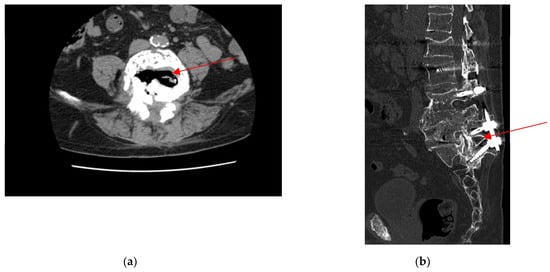

2.3. Admission to Infectious Diseases Unit

2.4. Neurosurgery Evaluation

| Present case | 80/M | Neuropathic metatarsalgia (8 w) | Permanent dental prosthesis | Discitis L3-L5 | No | (1) V. parvula (2) Not performed | S: Penicillin G, ampicillin/sulbactam, ceftriaxone, ciprofloxacin, gentamicin, vancomycin R: Piperacillin, ceftriaxone, azithromycin | Amoxicillin/clavulanic acid (6 w) | No | Cure |